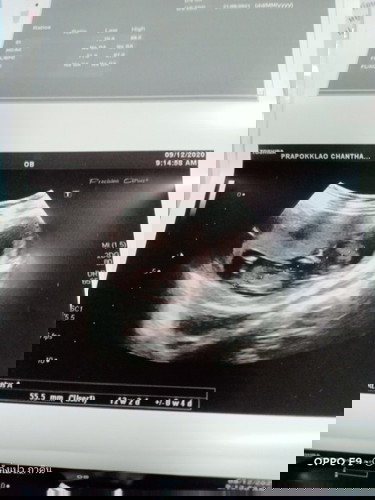

แม่บ้านไหนเป็นบ้างไหมค่ะ คือถ้านับตาม เดือนมาวันแรก ตอนนี้ก็จะได้ 14w แต่พอไปอัลตร้าซาวด์แล้ว น้องได

แม่บ้านไหนเป็นบ้างไหมค่ะ คือถ้านับตาม เดือนมาวันแรก ตอนนี้ก็จะได้ 14w แต่พอไปอัลตร้าซาวด์แล้ว น้องได้แค่ 12w2d บันทึกประจำเดือนทุกครั้งเลย ผิดพลาดตรงไหนมีใครพอรู้บ้างคะ

กำหนดตาม ปจด ค่ะแม่ อัลตร้าซาวด์คำนวณตามขนาด+น้ำหนักน้อง ไม่ตรงเท่า ปจด ค่ะ ของเราคลอดตอน 40+3 weeks ซาวด์ครั้งล่าสุดคือ 40 weeks น้ำหนักตามซาวด์คือ 2800g = 36 weeks+ แต่น้องคลอดจริง 2995g ค่ะ ซึ่งเป็นน้ำหนักปกติตามเกณฑ์ ตอนนี้น้อง 3 เดือนกว่า แข็งแรง สมบูรณ์ พัฒนาการดีมาก ปล. ปจด เรามาปกติค่ะ อาจารย์หมอนับตาม ปจด ครั้งสุดท้าย แล้วเรารู้วันปฏิสนธิด้วย พอดีเดือนนั้นมีอะไรกับสามีแค่ครั้งเดียว อายุครรภ์เราตรงตามนั้นค่ะ แต่ใบซาวด์จะเร็วกว่า 3 วัน

Đọc thêmยึดอายุครรภ์ตามใบซาวด์ช่วงแรกที่ฝากครรภ์จะแม่นยำสุดค่ะ ยิ่งอายุครรภ์เยอะขึ้นจะในใบซาวด์จะคลาดเคลื่อนเยอะ เพราะเครื่องจะคำนวณอายุครรภ์ตามขนาดเด็กค่ะ ของเรา 14 w++ เหมือนกัน แต่ขนาดเด็กได้ 15w+ จากการซาวด์ค่ะ ซึ่งของเราถือว่าขนาดเด็กเป็นไปตามอายุครรภ์ค่ะ คุณแม่ไม่ต้องตกใจนะคะ ถ้าคุณหมอแม่ได้บอกว่ามีปัญหาว่าน้องตัวเล็กกว่าเกณฑ์ ถือว่าปกติค่ะ ^^

เราก็เป็นค่ะ จดประจำเดือนทุกครั้งเหมือนกัน แต่อายุครรภ์จริงช้ากว่าประมาณ2อาทิตย์ เราก็นับเอาตามที่หมอซาวด์ค่ะ เพราะมันเป็นข้อมูลแน่นอนกว่า เพราะวัดจากขนาดตัวและน้ำหนักของลูกเราน่ะค่ะ

หมอวัดจากขนาดของทารกหรือเปล่าค่ะ เครื่องอุลตร้าซาวด์ คำนวณตาม ขนาดของทารกหรือเปล่า เพราะของเรา ก็เป็นค่ะ ถ้านับตั้งแต่ ปจด หมด จะ12 สัปดาห์ แต่พอไปซาว ขั้นเป็น13 สัปดาห์